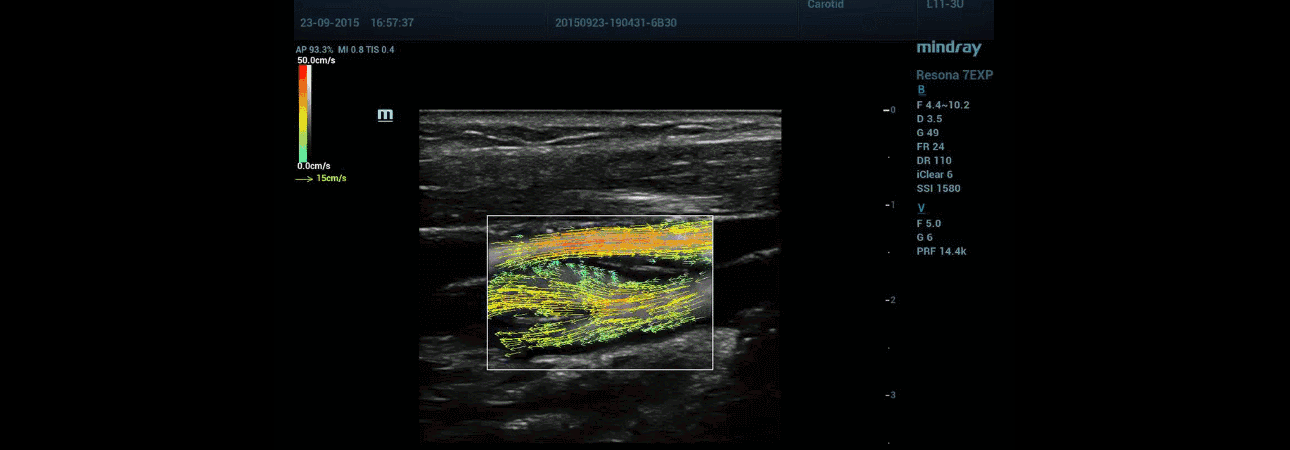

Doctor Pedro Jose Forcada is a renowned expert clinician as well as research academician in cardiology, holding senior positions in Latin America's most prestigious academic societies and universities. Dr. Forcada's lecture on "Re-stratification of Cardiovascular Risk through Ultrasound" explored the very frontier of ultrasound application in the cadiovascular field. He spoke highly of Mindray's Resona 7 Ultrasound System's vascular research feature V-flow.

V-flow is very helpful in vessel analysis. Many of my students are amazed to see it when I show them in class. V-flow shows many details that are impossible for traditional color Doppler to reveal.

Dr. Pedro Jose Forcada

President of Artery Latin America

Mindray's Resona 7 Ultrasound System enhances clinical research capabilities with the revolutionary V-Flow for vascular hemodynamics evaluation in addition to the supreme image quality.

WHAT IS V-FLOW?

Resona 7's V-flow feature is a novel visualization of blood flow, in which color arrows are displayed, instead of the color map of a conventional Doppler ultrasound image. With V-flow, Resona 7 delivers a technology that dynamically visualises blood flow.

The V-Flow feature displays the fluidity with dynamic arrows indicating the flow process, rather than a series of static images, with both the magnitude and direction of the flow measurable at any location in the vessel, avoiding the inconvenience of angiography.

To derive the direction of flow velocity, multi-directional transmissions and receptions are employed. A true velocity with accurate direction calculated via angle-compounding technology, shows an example where compounding and regression analysis of two angles is applied giving more angles. This is supported by innovative display technology with colour arrows.

Clinical results show that V-flow gives much more detail with different types of flow in the carotid artery, compared to conventional ultrasound colour flow mapping (CFM).